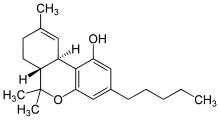

- Cannabis

- Hashish